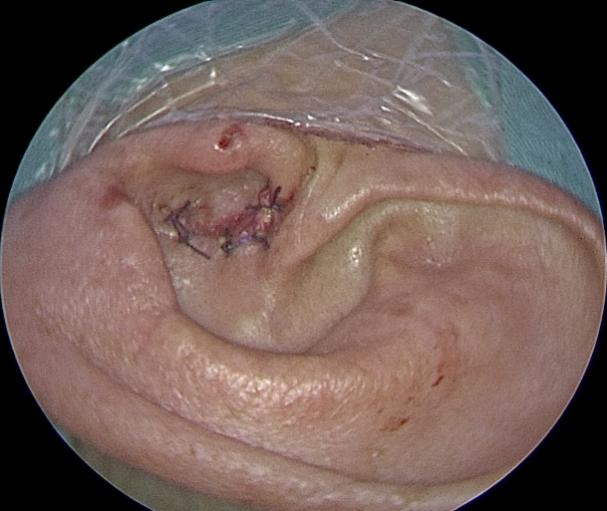

2023年2月16日,宋正川副教授负责麻醉,手术室高明姬、张帅老师配合手术,吴宝俊、李阳副教授在耳内镜下完整切除骨性耳道皮肤及鼓膜,去除听锤骨、砧骨及镫骨,采用持续灌流-水下耳内镜技术完成外耳道扩大成形,显露颈内动脉、颈静脉球、面神经水平段和垂直段后,轮廓化内听道的前、下、后壁,直至内耳门,完全显露并切除耳蜗及内听道肿瘤,王军利、胡新成主治医师取腹部脂肪填塞术腔,关闭耳道。术后患者面神经功能完好,无脑脊液漏,术后7天安全出院。